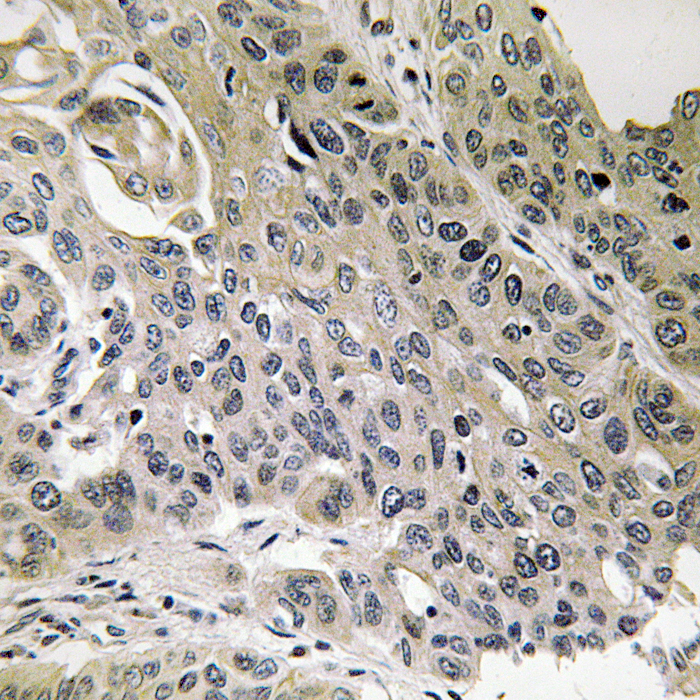

Immunohistochemical analysis of MRPS7 staining in human lung carcinoma formalin fixed paraffin embedded tissue section. The section was then incubated with the antibody at room temperature and detected using an HRP conjugated compact polymer system. DAB was used as the chromogen. The section was then counterstained with haematoxylin and mounted with DPX.